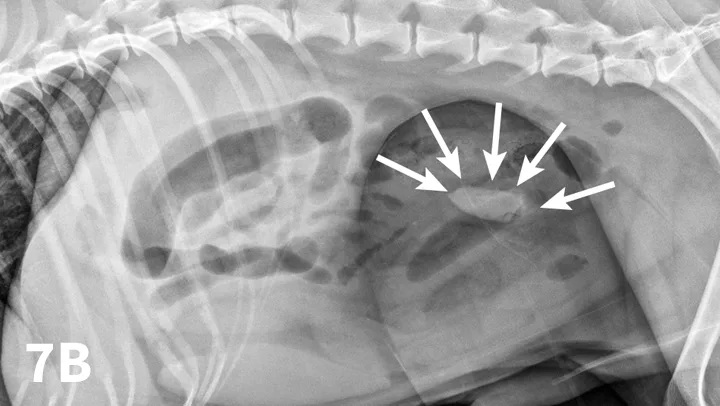

A ventrodorsal abdominal radiograph showing a round metallic object in the small intestine.

FIGURE 1

VD abdominal radiograph of a 1-year-old cat with a 2-day history of vomiting and a nonobstructing metallic foreign body. A coin with a radiolucent center caused by erosion is present within the small intestinal loops in the right midabdomen. No dilated loops of small intestine are seen to indicate mechanical obstruction.